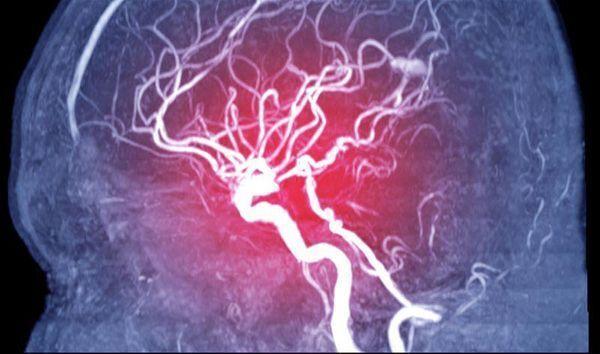

Tại sao COVID-19 có thể gây đột quỵ, dự phòng đột quỵ hậu COVID-19 ra sao?

Tỷ lệ bệnh nhân đột quỵ trong thời gian đang mắc COVID-19 từ 0,9 đến 2,7%, cao gấp 7 lần so với nhiễm virus khác như influenza (cúm), song hậu COVID-19 chỉ nên khám tầm soát khi có yếu tố nguy cơ. PGS.TS.BS Nguyễn Huy Thắng, Phó chủ tịch Hội Đột quỵ Việt Nam cho biết như trên, hôm 26/3.

Đối tượng, nguyên nhân và cách điều trị nhồi máu cơ tim, đột quỵ hậu COVID-19

Sau khi khỏi COVID-19, người bệnh có thể phải đối mặt với tình trạng đột quỵ hoặc nhồi máu cơ tim. Vì vậy, việc tìm ra phương pháp phòng ngừa là mối quan tâm lớn của các F0 lành bệnh? ThS.BS Đặng Huỳnh Anh Thư – Phó Trưởng Bộ môn sinh lý, Sinh lý bệnh miễn dịch, Đại học Y dược TPHCM sẽ giúp bạn đọc giải đáp những lo lắng này.

Hậu COVID-19 làm gia tăng nguy cơ nhồi máu cơ tim, đột quỵ não

Bên cạnh các tổn thương ở phổi, các triệu chứng tim mạch cũng ghé thăm người bệnh ở giai đoạn hậu COVID-19. ThS.BS Đặng Huỳnh Anh Thư, Bộ môn Sinh lý – Sinh lý bệnh Miễn dịch, Đại học Y dược TPHCM sẽ giải đáp sâu hơn về vấn đề này trong video dưới đây.